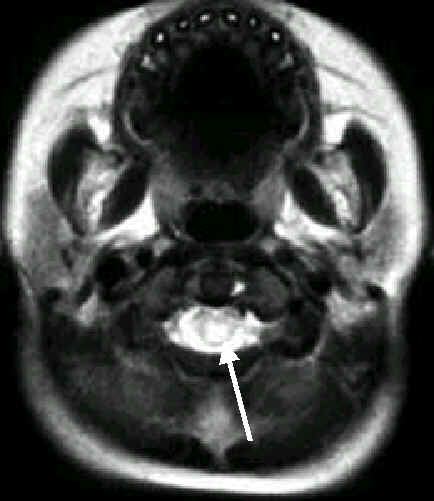

4歲男孩,手足口疾病合併腦炎

腦炎侵犯

中腦的中央

(箭頭所指變亮之處)

橋腦的後面

(細長箭)

及小腦齒狀核(粗短箭)